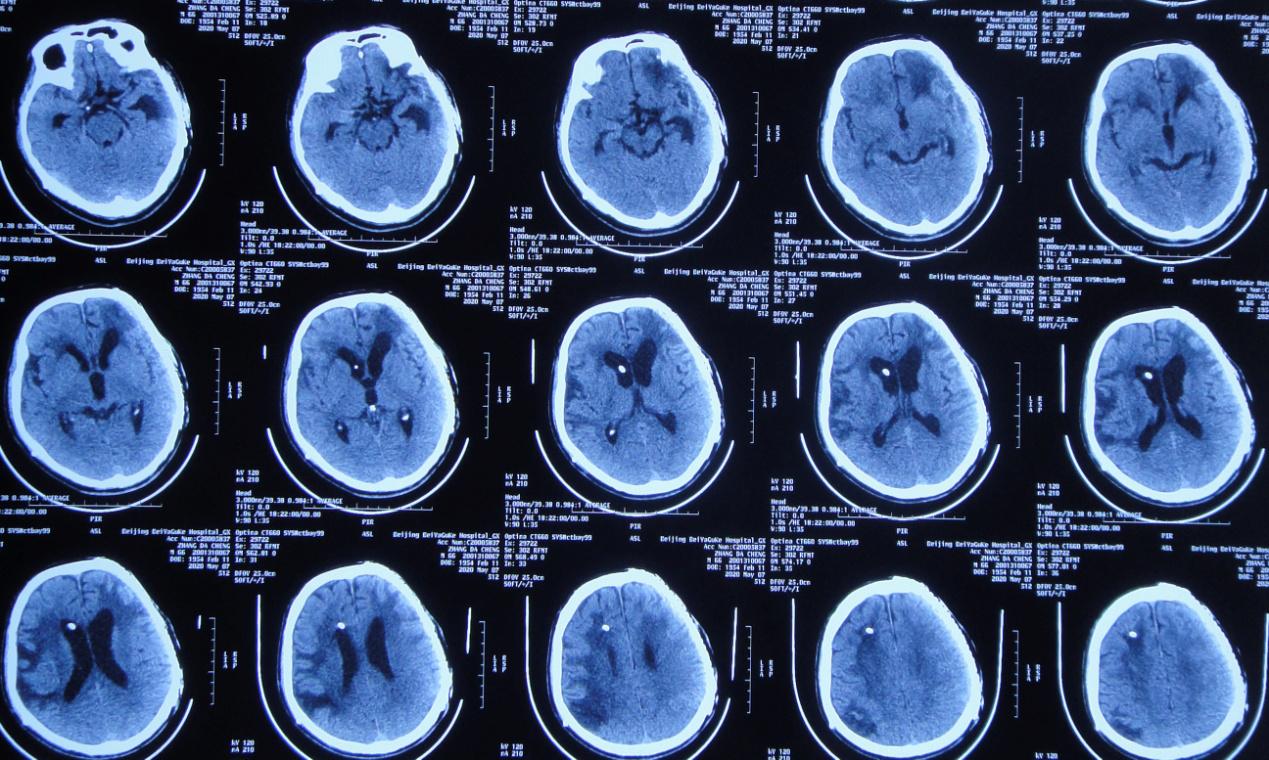

患者2019年7月10日骑电动自行车不慎与大货车相撞,当时意识模糊,可简单对答,四肢可见活动。由120急送至当地安徽省六安市某医院,行头颅CT示大脑多发挫伤(片子丢失),给予甘露醇等脱水治疗,效果差,意识明显加重,呼之不应,呈昏迷状态。当日急转入上级的安徽省某知名省级三甲医院,行头颅CT( 图-1 )示左颞叶脑挫伤伴血肿形成,右额叶脑挫伤,蛛网膜下腔出血,脑疝。

图-1: 2019年7月10日术前头颅CT